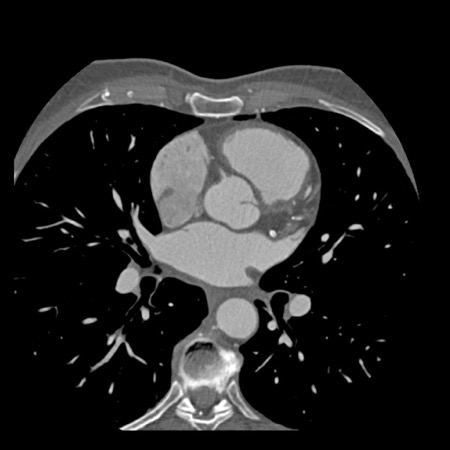

Modifier S – stent

The presence of a stent is indicated by modifier “S”.

Examples

- If a patient has a stent, showing no in-stent restenosis and a mild

(25-49%) stenosis in the coronaries, this patient classifies as CAD-RADS

2/S. - Similarly, a patient with no in-stent restenosis but severe (70-99%)

stenosis in a coronary other than LM classifies as CAD-RADS 4A/S. - If there is a severe (70-99%) in-stent restenosis in a coronary other

than LM, this patient classifies as CAD-RADS 4A/S. - If the stent is non-diagnostic and there is no >49% stenosis present

in the coronaries, the patient classifies as CAD-RADS N/S.

Note: the location of the stenosis does not matter, when using

CAD-RADS.

What matters is that the patient has a severe stenosis and needs further

management.

Please note: total coronary plaque burden should also be added and is

placed before the modifier S.